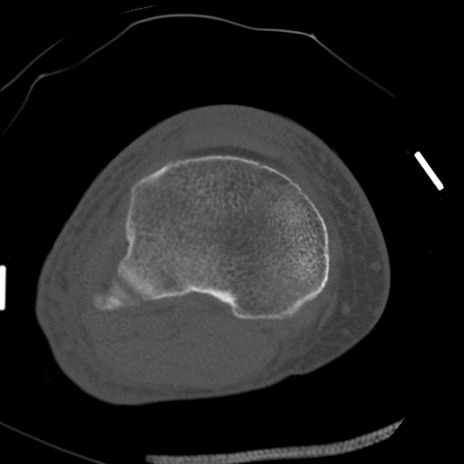

症例28 右膝関節CT(横断像)

右膝関節CT